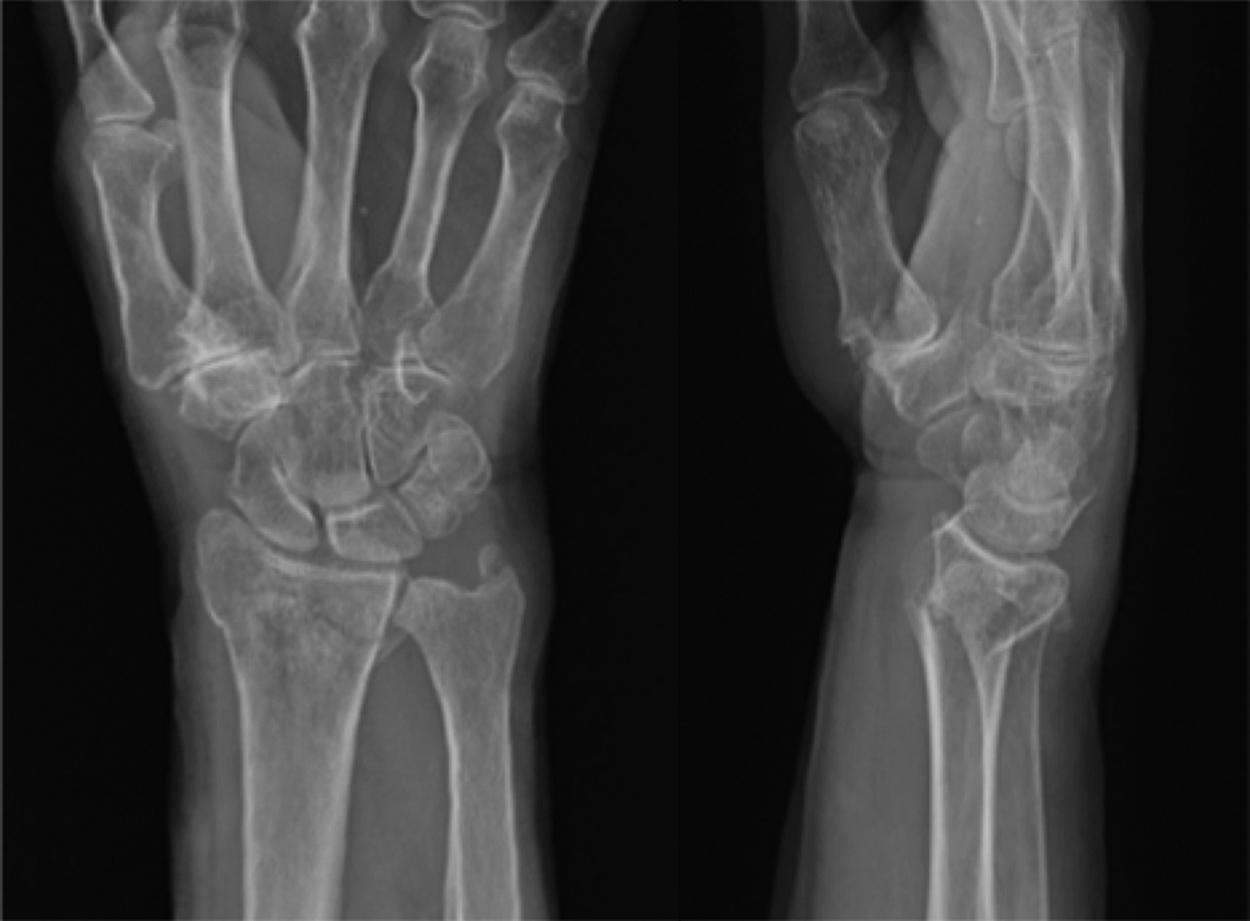

A 61-year-old male fell while walking his dog, sustaining a left, displaced DRF ( Fig. 1 A ). This was successfully treated with closed reduction ( Fig. 1 B), cast immobilization, and physiotherapy ( Fig. 1 C). Two years later, he slips on ice, fracturing his right distal radius ( Fig. 2 ). What interventions could have been employed following his first fracture to decrease the risk of his second, contralateral fracture?

Fig. 1, Right distal radius fracture sustained following a ground level fall. Initial radiographs (A) showing a displaced fracture, which was managed nonsurgically (B and C).

Fig. 2, Subsequent left distal radius fracture sustained from another ground level fall.